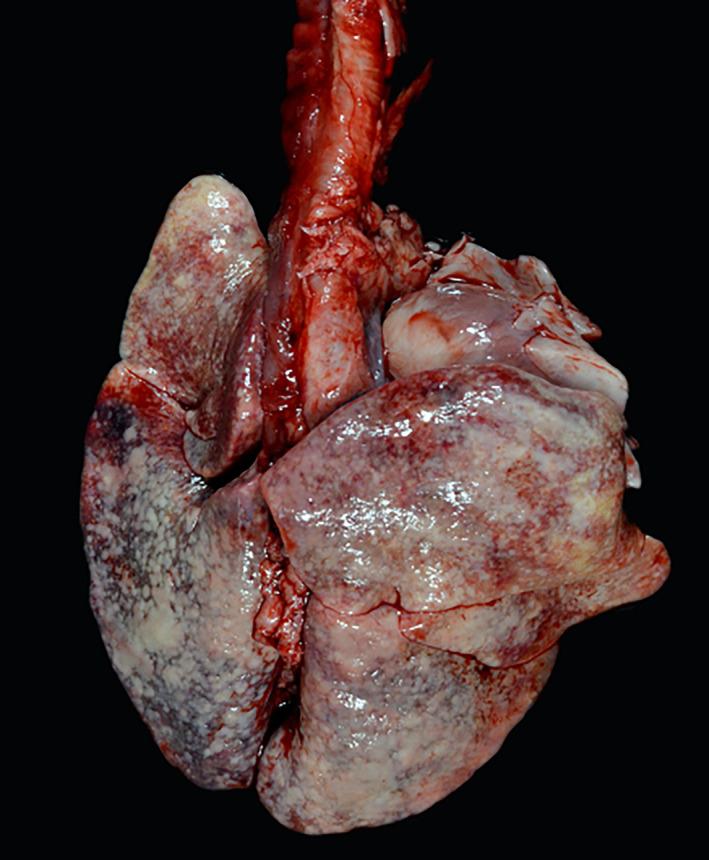

Sibling female and male Chihuahuas were evaluated for a 9-month history of tachypnea that failed to respond to fenbendazole, doxycycline, amoxicillin-clavulanate, and prednisone. Physical examination identified tachypnea, hyperpnea, and harsh bronchovesicular lung sounds. Fundic examination disclosed diffuse chorioretinitis, manifested as multifocal chorioretinal granulomas in the female dog and occasional chorioretinal scars in the male dog. Thoracic radiographs indicated moderate to severe interstitial to broncho-interstitial infiltrates in both dogs. Serum and urine antigen and antibody testing in the female dog failed to identify infectious agents, but cytologic assessment of hepatic lymph node, liver, and splenic aspirates identified Pneumocystis trophozoites. Infection was confirmed in both dogs by 28S rRNA PCR sequencing from multiple tissue samples. The female dog responded well to trimethoprim-sulfamethoxazole, but the male dog was euthanized because of liver failure, presumably related to antimicrobial treatment.

两只雌性和雄性吉娃娃犬因呼吸急促就诊,病史 9 个月,曾接受芬苯达唑、多西环素、阿莫西林克拉维酸和泼尼松治疗,但未见改善。体格检查发现呼吸急促、过度通气和粗湿啰音。眼底检查显示弥漫性脉络膜炎,表现为雌性犬的多发性脉络膜视网膜肉芽肿和雄性犬偶尔的脉络膜视网膜瘢痕。胸部 X 线片显示两只犬均存在中重度间质性至支气管间质性浸润。雌性犬的血清和尿液抗原及抗体检测未能识别出病原体,但对肝门淋巴结、肝脏和脾脏抽吸物的细胞学评估发现了卡氏肺孢子虫滋养体。通过对多个组织样本的 28S rRNA PCR 测序,在两只犬中均证实了感染。雌性犬对甲氧苄啶-磺胺甲噁唑反应良好,但因肝功能衰竭,雄性犬被安乐死,可能与抗菌药物治疗有关。